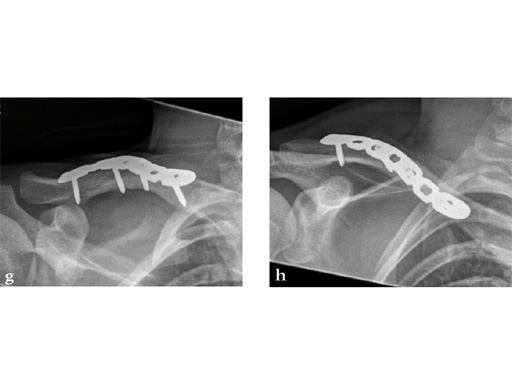

Case 2: a 29-year-old man sustained a midshaft clavicle fracture while playing soccer.

Case provided by Norbert Sdkamp and Martin Jaeger, Freiburg, Germany